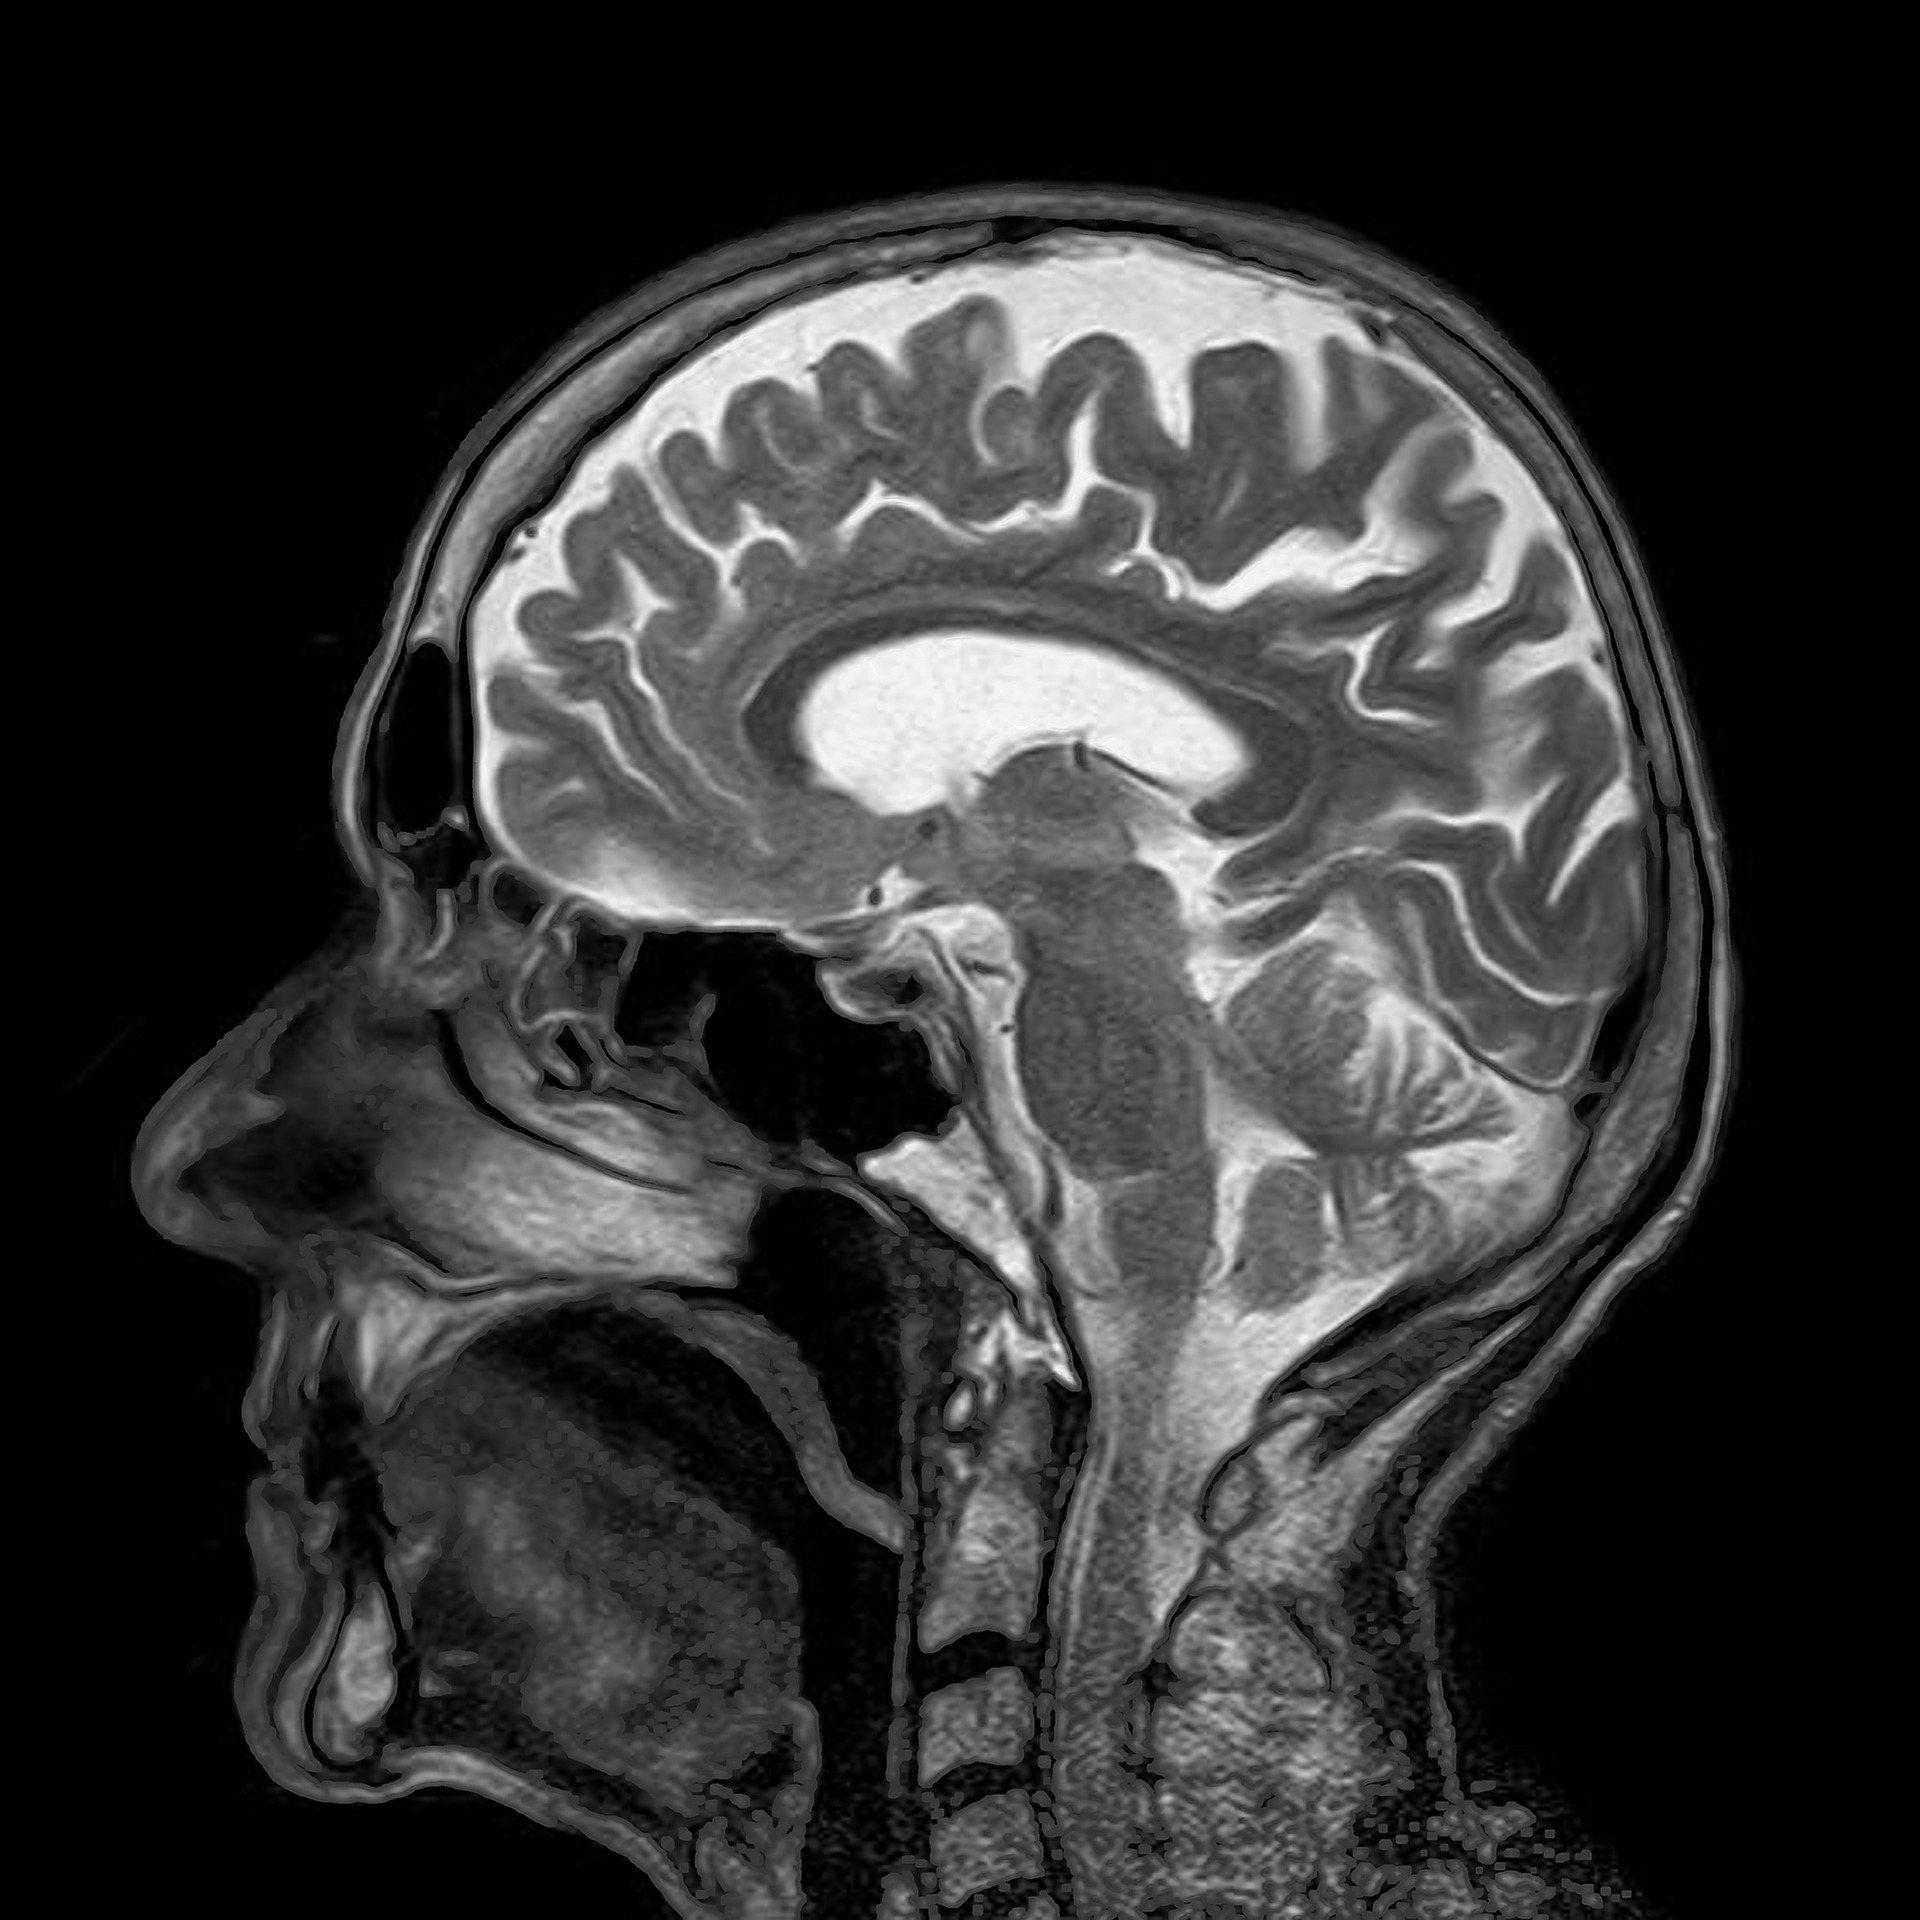

Mental symptoms and MRI examination

“Every participant underwent a thorough investigation of mental symptoms and magnetic resonance imaging (MRI) of the brain, focusing particularly on central parts of the brain, such as the hippocampus and amygdala — areas we know are often implicated in altered cognitive function in other pathological conditions,” says Mats Holmberg, Chief Physician and researcher in endocrinology, who is the study's lead author.

What the scientists show in their study, published in The Journal of Clinical Endocrinology & Metabolism, is that central parts of the brain shrink when hormone levels are high, and that these parts largely resume their normal size when the hormone levels normalize and symptoms subside.